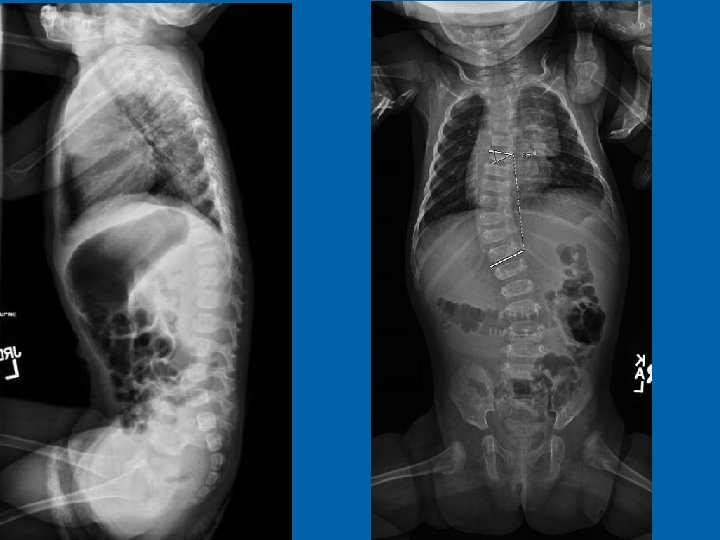

Progressive NF 1 Scoliosis August 12, 2013

August 12, 2013

27